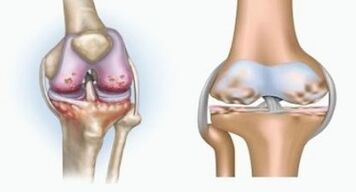

Beide Pathologien beeinflussen die Gelenke, unterscheiden sich jedoch in der Art der Veränderungen.

Mit Arthritis

Arthritis ist eine Entzündung des Bindegewebes, eine Synovialmembran, die viele Gefäße enthält und einen lymphatischen Fluss liefert. Der entzündliche Prozess führt zu einer Verletzung der Ernährung von Gelenkgeweben, wobei die Produktion von Gelenkschmierung - Synovialflüssigkeit begrenzt ist.

Mit Arthrose

Arthrose ist ein degenerativ-divophischer Prozess, der mit der Zerstörung des Artikulationsknorpelgewebes verbunden ist. Der Knorpel wird allmählich zerstört, trocken, der Abstand zwischen den Gelenkknochen nimmt ab, was die Ursache für Schmerzen ist. In schweren Formen beeinflusst die Zerstörung Knochen. Sie werden poröser, sie verlieren ihre Dichte, sie werden zerbrechlich.

Was ist zum Beispiel der Unterschied zwischen Arthritis und Arthrose des Kniegelenks? Bei Arthritis tritt die Synovialschicht von Gelenkgeweben auf. Dies führt zu einer Erhöhung der Gelenktemperatur.

Die Artikulation nimmt zu, ein anhaltendes Schmerzsyndrom wird entwickelt, was während der Bewegung intensiviert wird. Bei Arthrose tritt der Schmerz erst nach körperlicher Aktivität auf.

Der Unterschied zwischen Arthritis und Arthrose der Finger und der Hände der Hände besteht darin, dass die erste Krankheit geheilt und die zweite nicht. Bei Arthritis werden die Synovialgehäuse und die Artikulationskapsel berührt.

Die Niederlage des Knorpels und des Knochengewebes erfolgt nur in den letzten Stadien in einem nachlässigen Zustand. Bei Arthrose ist das Knorpelgewebe zuerst betroffen, und dann ist die Entzündung der Synovialmembran sekundärer Herkunft, dh sich vor ihrem Hintergrund.